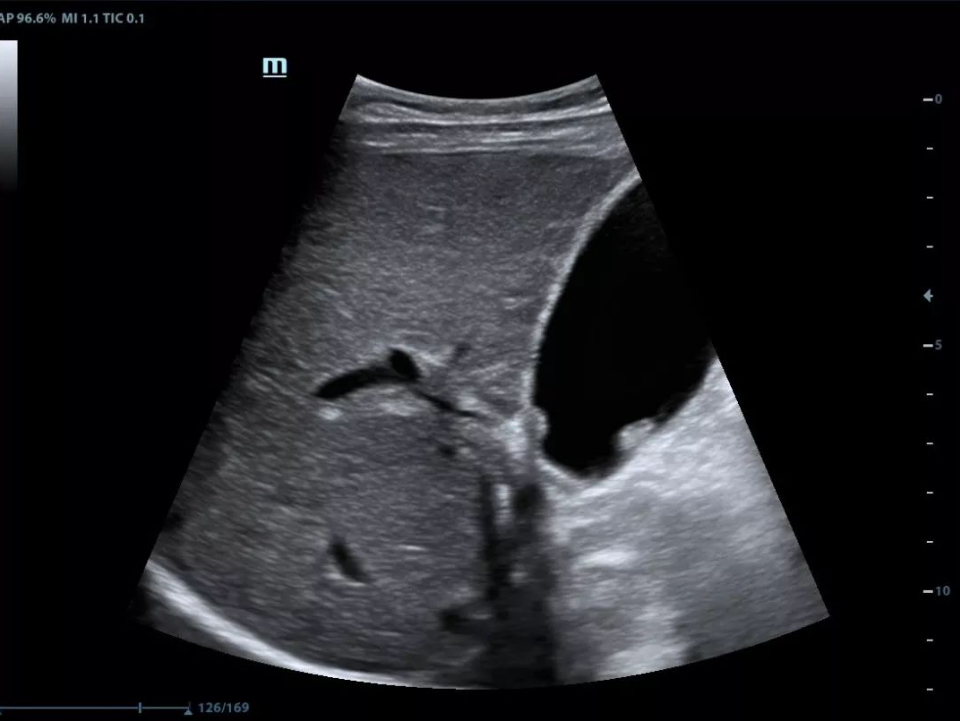

Single crystal transducers with 3T technology

Mindray's unique single crystal transducers with 3T technology

(Triple-matching layers, Total-cut design and Thermal control) provide a wider bandwidth to simultaneously offer better penetration and higher resolution. Integrating the brand-new single crystal volume, convex and phased array transducers with the system, X-Insight makes an optimum scanning solution in OB/GYN, ABD, Cardiology, and more.

Gallbladder polyp

Fetal heart sclerosis

Four chamber view